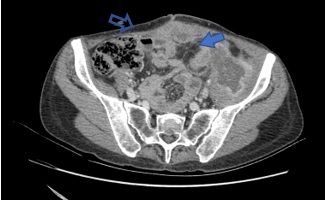

Una nueva TC de estadificación demostró la infiltración del tumor al músculo ilíaco y nervio crural izquierdo. La arteria ilíaca externa se encontraba en íntimo contacto sin invasión aparente. Se objetivó una colección sobre la pared abdominal con relación a la cicatriz mediana (Fig. 1). No había evidencia de diseminación a distancia. Los marcadores tumorales CEA y CA 19-9 fueron normales.

Fig. 1. a) Engrosamiento del colon descendente con fistulización hacia el músculo ilíaco izquierdo y colección en su interior (flecha sólida). b) Colección detrás de la mediana (flecha vacía).